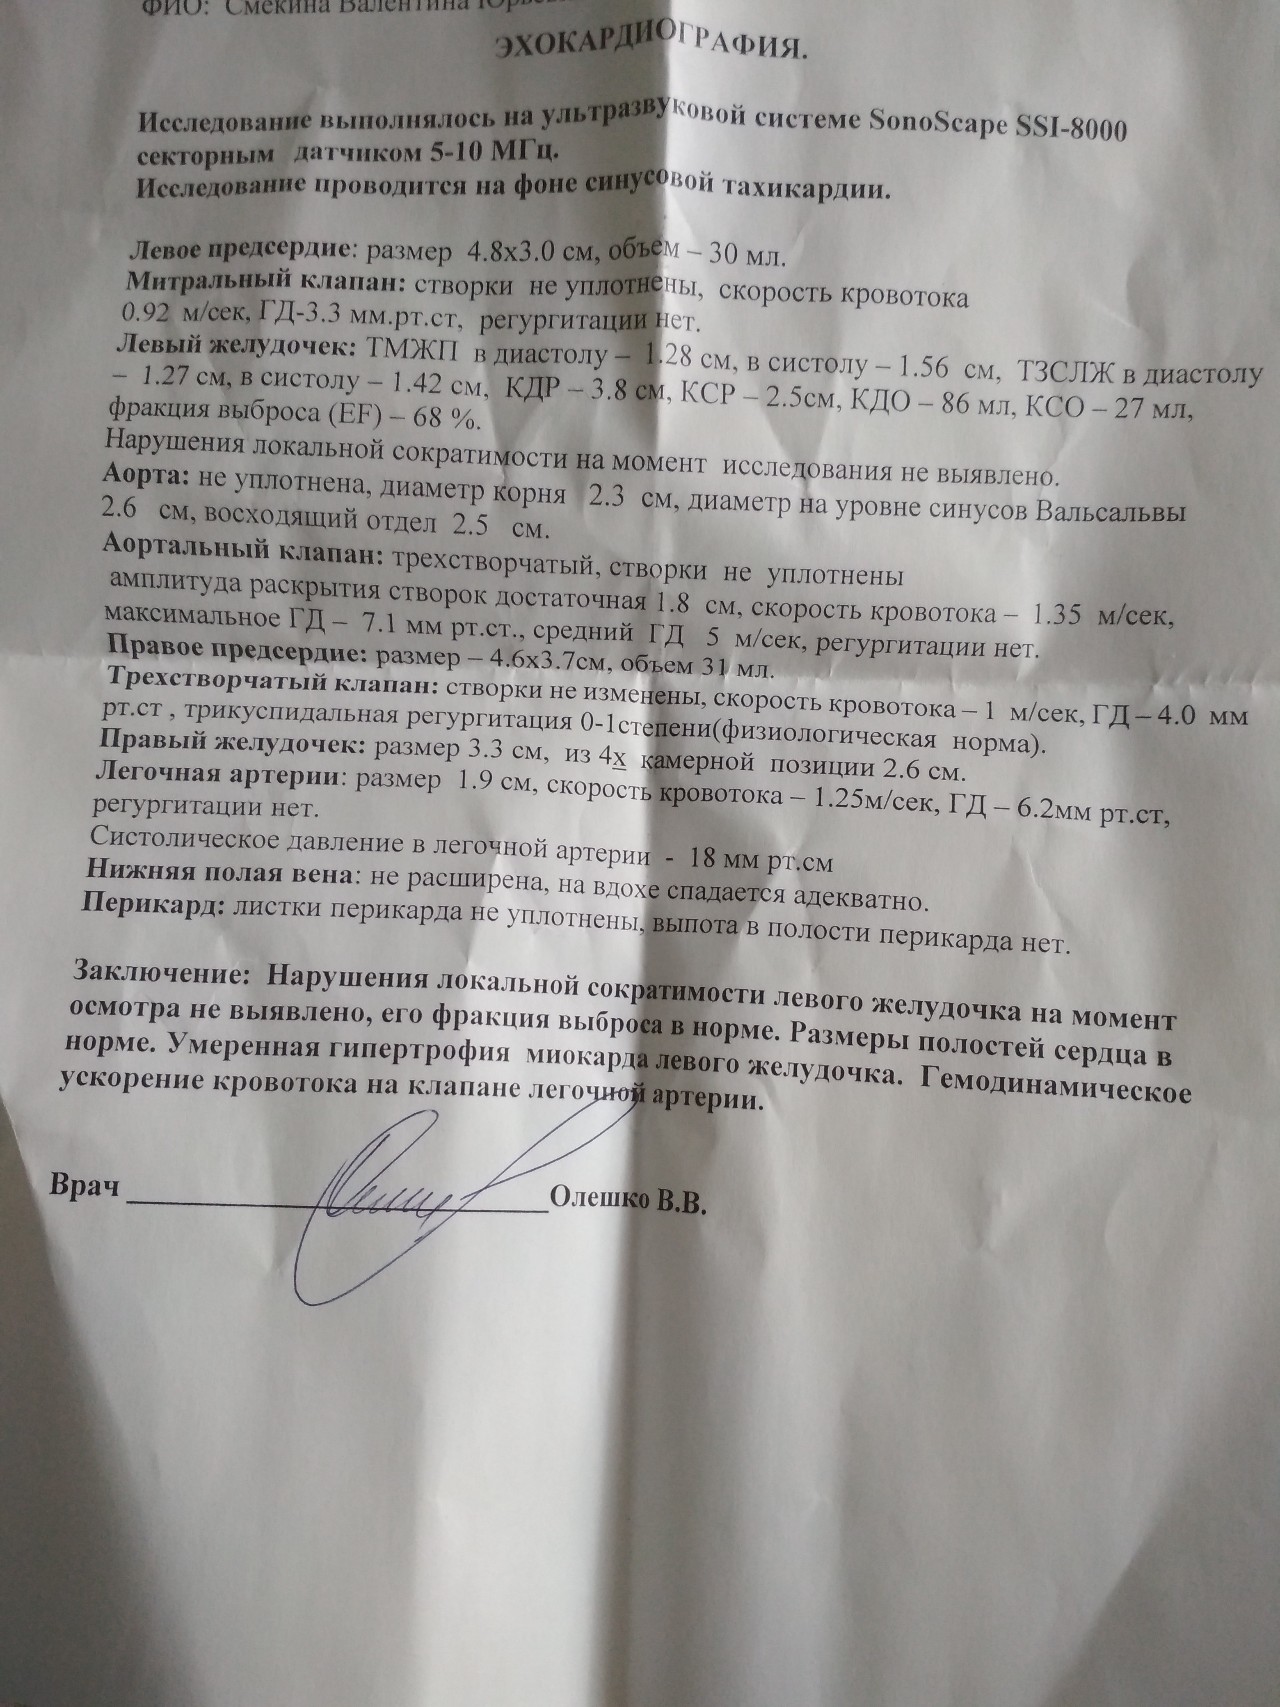

Нормальный диаметр корня аорты: медицинские нормы и отклонения